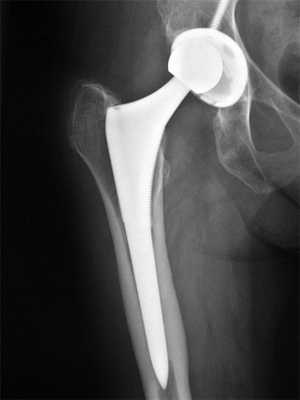

- После действия анестезии и широкой антисептической обработки кожных покровов, коагулятором или скальпелем выполняется разрез по межвертельной линии до открытия сустава.

- Далее выполняется под правильным углом и уровнем пересечение бедренной кости в зоне шейки. Разверткой врач создает канал в подвергнувшемся остеотомии трубчатом элементе.

- Затем в созданный выпор вставляют клиновидную ножку, которая идеально должна совпадать с его параметрами, поэтому обработка данной кости должна пройти на безупречном уровне. На конусообразную верхушку ножки насаживается шаровидное тело имплантата.

- Сзади или спереди, в зависимости от примененного доступа, бедро смещают в сторону и приступают к подготовке вертлужной впадины. Используя долото и фрезы, специалист всецело удаляет гиалиновый хрящ с ее днища. Имплантат (чашу) вставляют в очищенное ложе. В него помещают полиэтиленовый вкладыш.

- Осуществляется вправление компонента бедра в чашку. После в рану ставится дренаж, рассеченные ткани ушиваются, на конечность накладывается повязка.